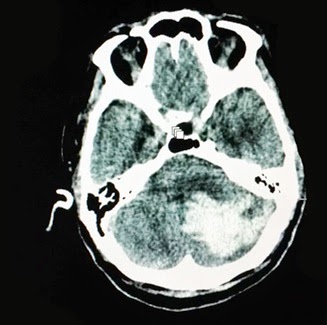

hemorragia subaracnóidea traumática é feito baseado na história de trauma

associada à hemorragia no espaço subaracnóideo documentada com Tomografia

Computadorizada de crânio.